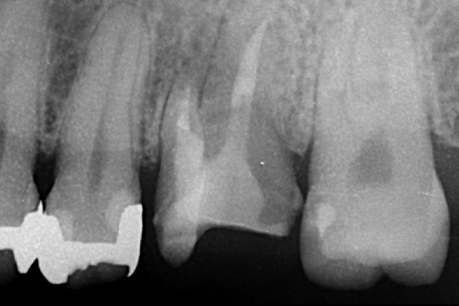

左上6番目

治療の内容:パーフォレーションにより根分岐部病変があり、根尖病変もある症例。歯内歯周病変で歯周病と根尖病変が合併している難治症例。根管治療後分岐部病変が治らなかったため遠心頬側根の歯根切除を行いその後近心頬側根が石灰化しておりそこの根尖病変も治癒が悪かったため歯根端切除も行った。歯周ポケットがなくなり、根尖病変も治癒傾向なため補綴処置を行なった。

治療の期間:8か月

回数:根管治療4回、コア1回、歯根切除1回、抜糸1回、歯根端切除1回、抜糸1回

金額:保険治療

治療のリスク・副作用:術後に歯根破折を起こしたり、清掃不良から歯周病や虫歯を作ることがある。